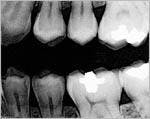

Recently, a patient came in to see me for a routine checkup. He reported some occasional pain in his lower left quadrant. In Figure 1, you will see a reproduction of the digital bitewing that we took in my office that day.

We noticed a vertical line running from the bottom of his amalgam restoration down to the pulp chamber. When we enhanced the image using the Clear-Vu tool in our DEXIS digital radiography system (see Figure 2), the fracture was clearly evident. We then took a conventional X-ray film, shot at regular speed and hand-developed at 68 degrees. By contrast, the vertical line was not evident on that film at all!